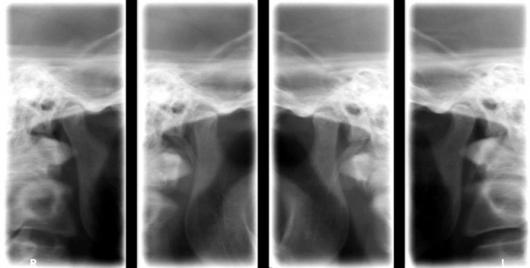

Radiografia A.T.M./ TMJ X-Ray

- dreapta cu gura inchisa cu gura deschisa - stanga cu gura inchisa cu gura deschisa